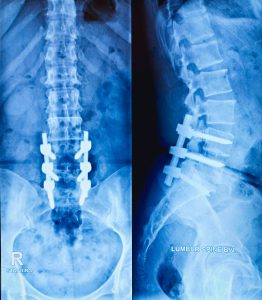

The sacroiliac joints are crucial connections between your sacrum (the triangular bone at the base of your spine) and your ilium (the largest bones of your pelvis). They provide stability and help transfer weight between your upper body and legs. When these joints become inflamed or dysfunctional—a condition often referred to as sacroiliitis or SI joint dysfunction—it can lead to significant discomfort in the lower back, buttock, and sometimes radiate down the leg.

- **Sacroiliac (SI) Joint:** The joint connecting the sacrum (base of the spine) and the ilium (pelvic bone).

- **Sacroiliitis:** Inflammation of one or both sacroiliac joints, often causing pain in the lower back, buttocks, or legs.